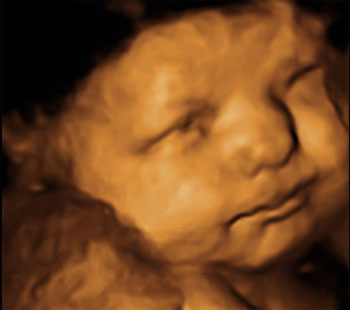

Baby-Kino und Ausflüge - Tagebücher aus der Schwangerschaft von Saskia aus Offenbach